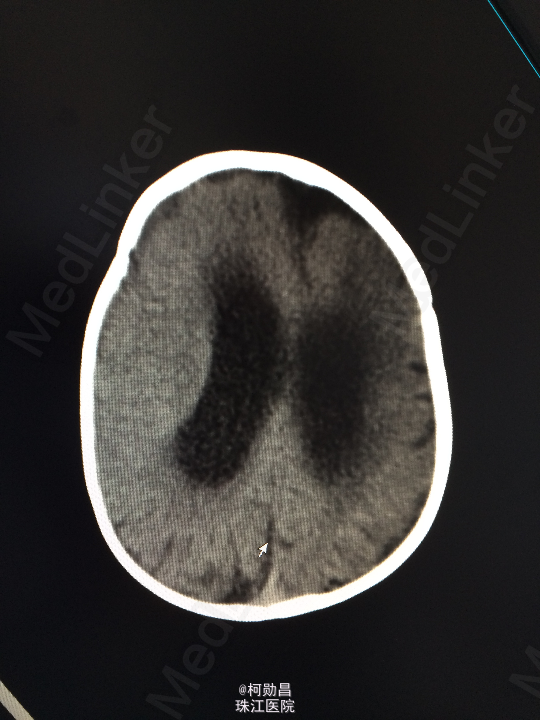

主诉:发热10天,抽搐3天 病史:患儿出生后8个月,因“发热10天,抽搐3天”入院,入院时体温39.3℃,神志不清,反应差。四肢肌张力增高,以双上肢肌力增高明显。病理征未引出。

查体:神志不清,四肢肌力增高 辅助检查:头颅CT提示脑积水并脑脊液外渗,幕上脑室扩张,右侧额颞叶硬膜下脑脊

诊断:化脓性脑膜炎伴脑积水 处理:予内科抗感染治疗,后行脑室腹腔引流术。